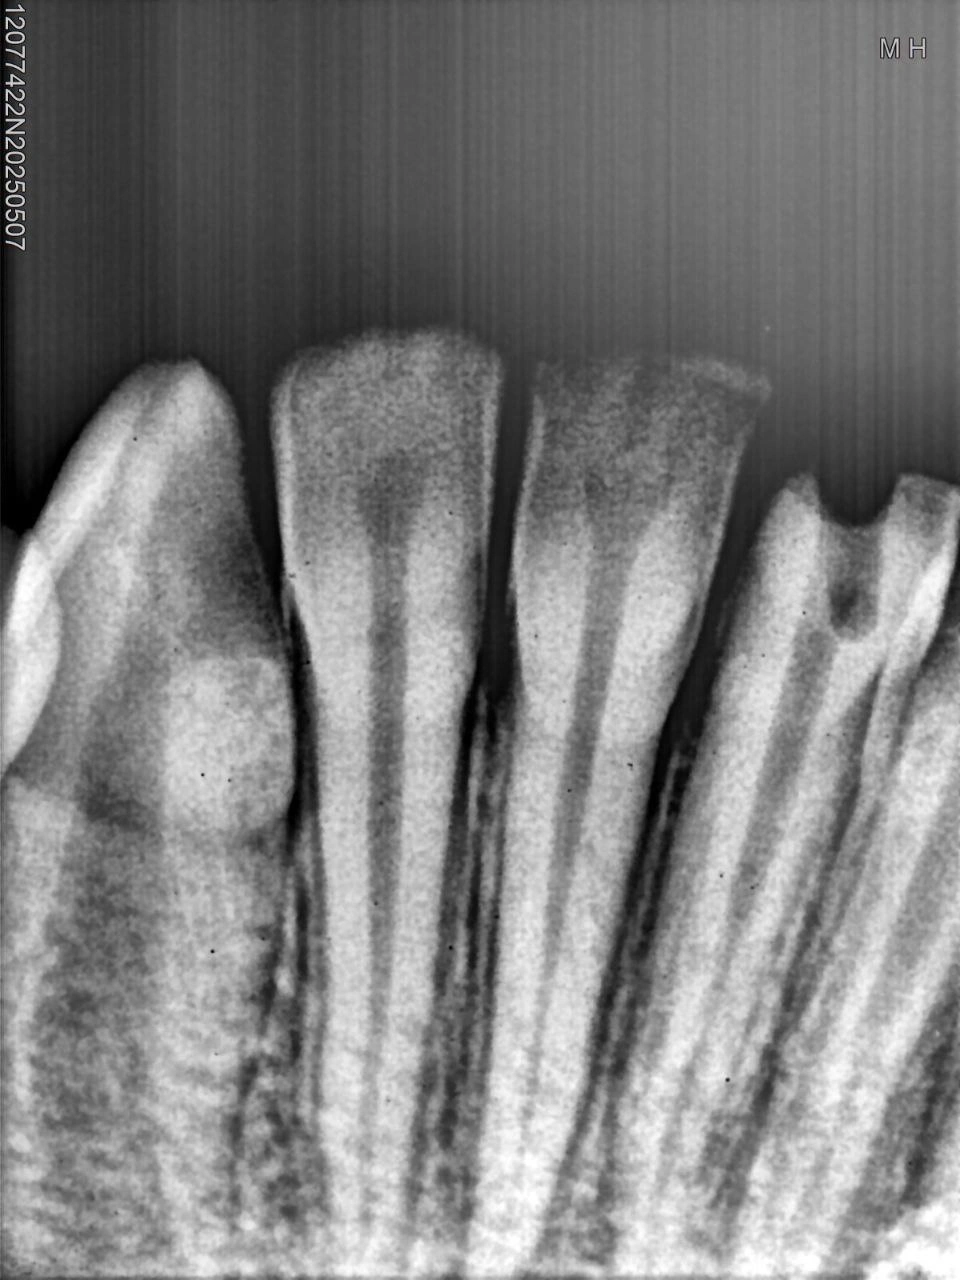

Pre-operative radiograph of the mandibular central incisors showing indication for root canal treatment.

Background: The patient presented with lower anterior teeth showing signs suggestive of pulpal necrosis and periapical involvement.

• Clinical examination revealed non-vital tooth most likely due to trauma

• Loss of lamina dura in the affected region

Treatment Plan: Based on the radiographic appearance and clinical correlation, root canal treatment was indicated.